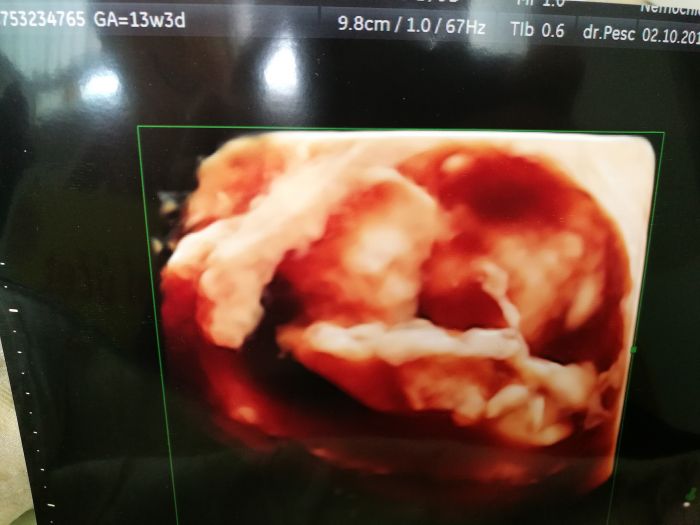

Ahoj devcata, tak hlasim, ze prvni screening dopadl skvele, jen mam vyssi riziko cukrovky 1:83, ale to mi je uplne fuk, mam si koupit nejaky doplnek stravy a byt v klidu. Vypada to na holcicku, ale nechtela se moc ukazovat, priste uz mi to rekne na 100%, mimco sebou strasne mrskalo, doktor se smal, ze ho snad ami nezmeri, poslouchali jsme srdicko, chlap byl uplne nadsenej. Velikost odpovida, takze termin zustava 6.4. Vysetreni bylo fajn, chlap se s panem doktorem zna z hokejbalu, jeho syn hraje s nasim v tymu a me pan doktor ucil na zdravce. Vubec nevim ceho jsem se tak bala. Vysledky mi jeste bude volat nejaka doktorka, ale podle zltrazvuku nam to vyslo bajecne.